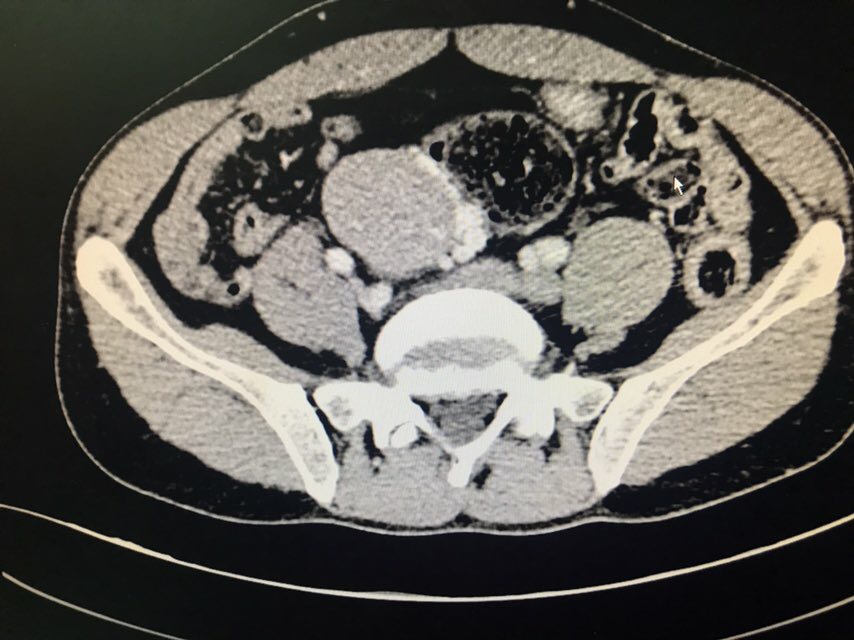

患者男性,43岁。主诉:发现盆腔占位1+月。现病史:患者1+月前于当地医院体检发现盆腔包块,于2018-08-28我院行泌尿系超声示:右侧髂窝实性占位伴钙化;2018-08-31我院行CT下腹部盆腔增强扫描示:下腹部及盆腔内多个软组织结节肿块影,肝右后叶上段囊肿;2018-09-07我院行病理检查示:盆腔肿瘤,倾向神经内分泌肿瘤,需行免疫组化染色检查;2018-09-07我院行膀胱超声示:超声引导下膀胱右侧盆腔内实性团块CNB。现患者为求手术治疗,于我院门诊就诊,以“盆腔肿瘤”收入我科。既往史无特殊。

查体:双侧腰部外形对称,皮肤无红肿,双肾区无叩痛,双肾下极未扪及,双输尿管行程区无压痛,膀胱区无隆起及压痛。双侧腹股沟区未扪及异常,无压痛;阴囊及尿道口未查。辅助检查:泌尿系超声(2018-08-28本院):右侧髂窝实性占位伴钙化;CT下腹部盆腔增强扫描(2018-08-31本院):下腹部及盆腔内多个软组织结节肿块影,肝右后叶上段囊肿;病理检查(2018-09-07本院):盆腔肿瘤,倾向神经内分泌肿瘤,需行免疫组化染色检查;膀胱超声(2018-09-07本院):超声引导下膀胱右侧盆腔内实性团块CNB。

患者膀胱右后方实性占位,穿刺活检倾向神经内分泌肿瘤,有手术指征。术中盆腔占位与周围重要组织器官粘连紧密,完整游离后整个创面较大,手术顺利,术后给予曲克芦丁脑蛋白水解物注射液2ml治疗。等待最终病理结果回报后制定下一步放化疗方案。